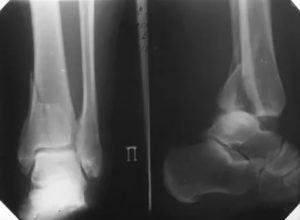

- Рентгенография. У детей старшего возраста при 2 и 4 типах перелома на снимках просматривается фрагмент метафиза, выявляется смещение ядер окостенения в эпифизарной зоне. У пациентов младшей возрастной группы и больных с остальными типами переломов изменения отсутствуют или нерезко выражены, поэтому в сомнительных случаях выполняют сравнительные рентгенограммы обеих конечностей.